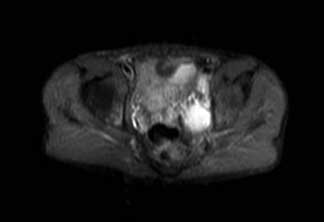

MRT - There is a ring enhancing multilobulated collection mainly

within the left adductor magnus muscle, this measures

approximately 30 cm (CC) X 5cm (AP). The collection extends

superiorly into the pelvis and involves the left obturator

internus muscle. There is abnormal marrow signal within the

posterior left acetabulum and inferior pubic ramus, within

the pubic ramus there appears to be an enhancing tract which

may represent a cloaca. No sinus tracts to the skin are

seen. No definite abnormal signal is seen within the femur.

Наиболее вероятны очаги туб. остита в своде левой вертлужной впадины и в левой седалищной кости.

Просмотрел все предоставленные исследовании и первый МРТ снимок показывает, что ни псоас и не прямая кишка не вовлечены в процесс. Медиальнее от псоас слева имеется абцесс идущий сверху. На втором боковом изображении белое пятно это сердце, потому что находится выше диафрагмы. Спереди передная стенка, а пятно сзади это начало абцесса.Третий и четвертые снимки показывают уровень таза и медиально расположенный многокамеральный абцесс идущий между мышцами.